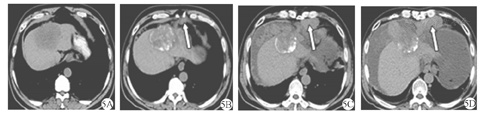

患者 男,57岁,乙型肝炎病史20余年。患者以"右上腹不适1周"为主诉入院。上腹部平扫CT(2015年10月21日)示:肝内Ⅳ段及Ⅷ段交界处可见8.2 cm × 6.2 cm团片状低密度区(图1A、图1B)。上腹部增强MRI(2015年10月22日)示肝左叶团块影,增强扫描病灶边缘不规则强化(图1C、图1D)。实验室检查:乙型肝炎表面抗原(HBsAg)阳性,甲胎蛋白(AFP)833.40 μg/L,癌抗原(CA)19-9 108.58 kU/L,肝功能Child-Pugh分级B级。临床诊断为原发性肝细胞癌,巴塞罗那肝癌分期(BCLC)B期。患者无介入治疗禁忌证,于2015年10月29日行肝动脉化疗栓塞术(TACE),术中造影见肝内肿瘤轻度染色(图2A),超选后肝右动脉予以碘化油5 ml +吡柔比星5 mg缓慢栓塞,辅助明胶海绵微粒(350~560 μm)50 mg+吡柔比星10 mg栓塞至肿瘤染色消失(图2B)。为明确病理诊断,术中经皮经肝超声定位下穿刺活检(16 G COOK活检针),术后病理(图3):肝细胞癌。术后第4天复查:AFP 263.50 μg/L,CA19-9 233.4 kU/L,肝功能基本正常。1个月后复查:AFP 712 μg/L,CA19-9 512.3 kU/L。于是,2015年12月7日再次行TACE,术中造影见肝肿瘤轻微染色(图4A),予以50 mg明胶海绵微粒(350~560 μm)10 mg+雷替曲塞2 mg+奥沙利铂50 mg栓塞肿瘤,造影见肿瘤染色消失(图4B)。第1次TACE术后1个月(2015年12月10日)复查上腹部CT示肝内见团片状、点状高低混杂密度影,较大切面为7.3 cm × 6.2 cm,局部突出于肝包膜之外,腹膜及肝被膜下见多发小结节状影,提示腹膜转移(图5A、图5B)。第1次TACE术后3个月(2016年2月14日)复查上腹部CT示肝内病灶较前缩小,腹膜多发结节状较前增多、增大(图5C);复查AFP上升至6 028 μg/L,腹水脱落细胞检查为腺癌。为控制腹膜转移瘤进展,患者口服索拉非尼(200 mg/次,2次/d)和腹腔灌注化疗(每3周腹腔灌注洛铂、雷替曲塞、香菇多糖及苦参碱)。第1次TACE术后6个月(2016年5月14日)复查上腹部CT提示肝内病灶缩小,坏死明显,但腹膜转移灶较前增多、增大,腹水较前增多(图5D);复查AFP >10 000 μg/L。患者于2016年6月20日不慎摔倒出现意识模糊伴发恶心呕吐,呕吐物为咖啡样物,随后出现心脏、呼吸骤停,临床死亡。

注:5A:术前;5B:术后1个月;5C:术后3个月;5D:术后6个月